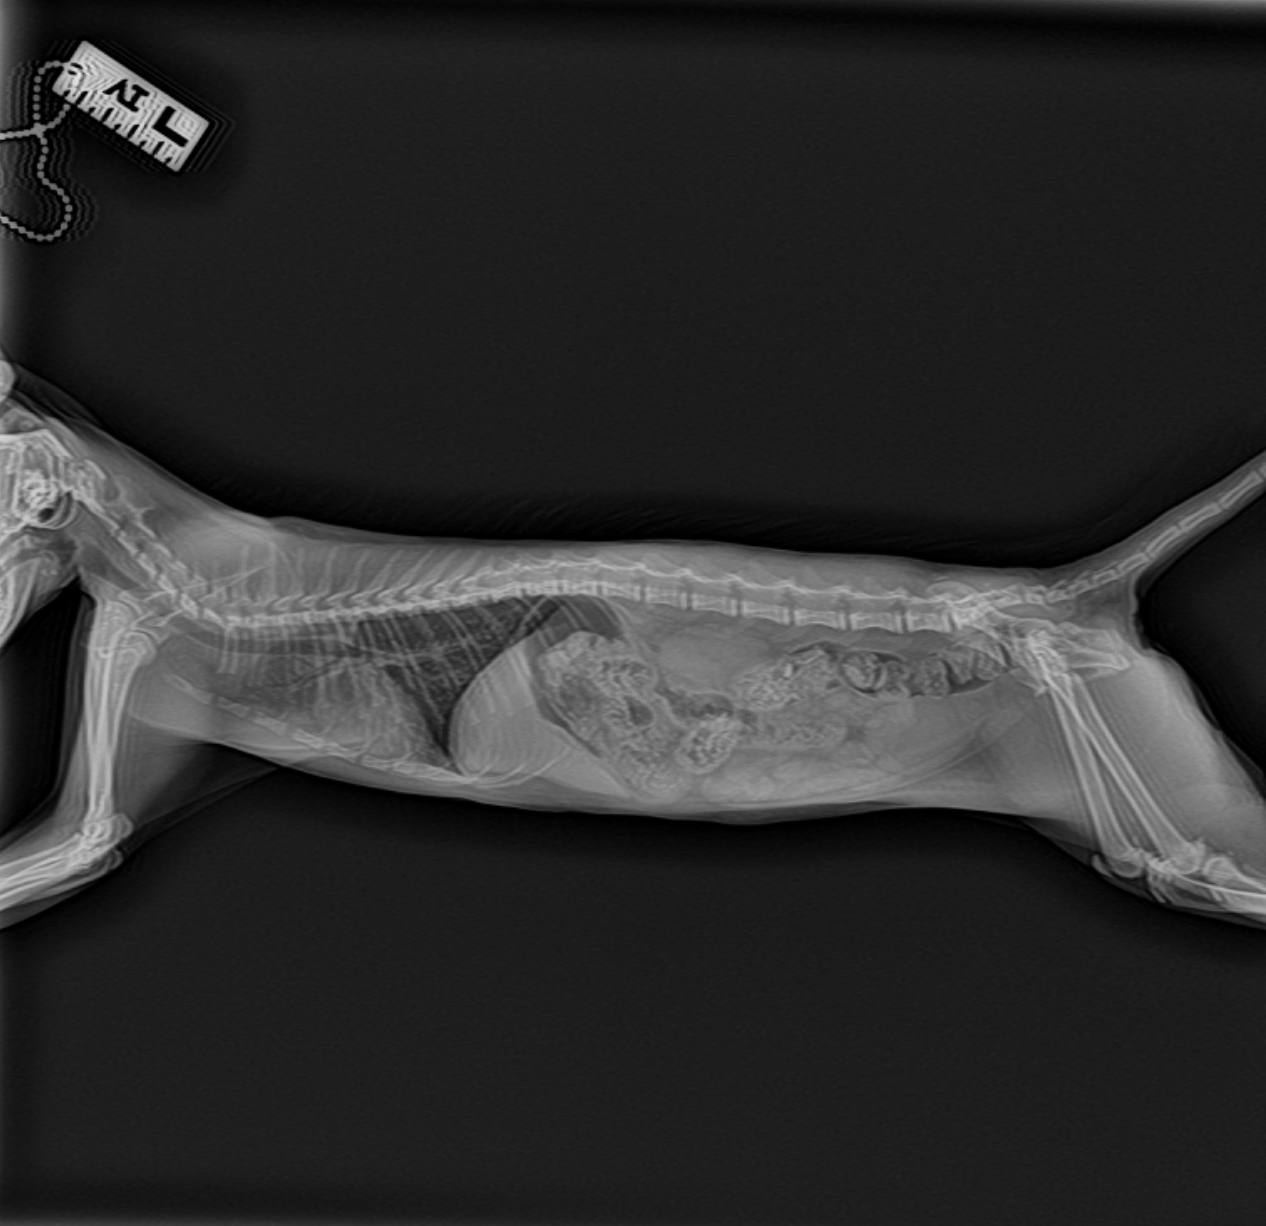

Багги еще сделали контрольный рентген в долг перед клиникой. Пока без видимых улучшений, скорректировали лечение, верим!

кашель продолжается, рентген пока не вдохновляет, есть подозрения на астму... 😔 Вкололи кортизон и наблюдают…